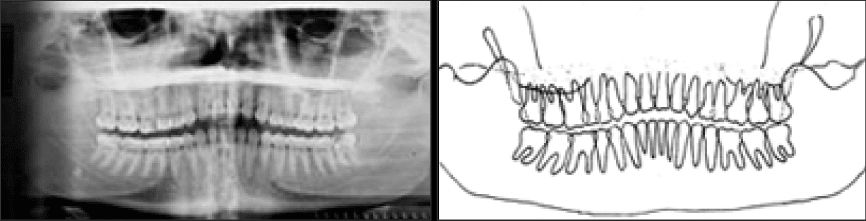

بينما إذا كان الذقن مرتفعا إلى الأعلى أكثر من اللازم تخرج الأسنان الأمامية من طبقة التصوير لجهاز الأشعة البانورامية وتظهر صورتها مشوهة ولاترى بوضوح.

في المقابل لو نزل الذقن أكثر من اللازم أثناء التصوير البانورامي فلن يتوافق محور فرانكفورت للرأس مع الخط الضوئي في الجهاز وستخرج الأسنان من طبقة التصوير وتظهر صورتها مشوهة (وكأنه مبتسم).